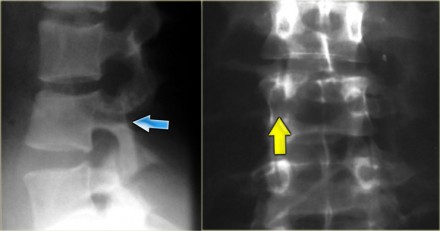

On the left images of a 21-year-old female who presented after sustaining a seatbelt type injury.

She had an exploratory laparotomy for repair of a ruptured duodenum.

There was no neurologic deficit.

First study the images, then continue reading.

What we see is a classic example of a chance fracture,

which is a three column injury with a horizontal orientation of the

fracture.

Continue with the CT-images.

What is unique about the Chance fracture is the

horizontal orientation, which is nicely demonstrated on the sagittal

reconstructions on the left.

Continue with the coronal reconstructions.

Also on the coronal reconstructions we can see the horizontal orientation of the fracture.